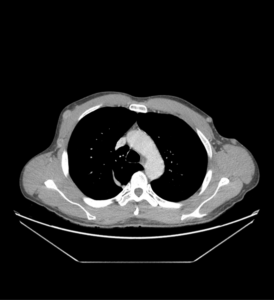

TC cervical y torácica

HALLAZGOS RADIOLÓGICOS